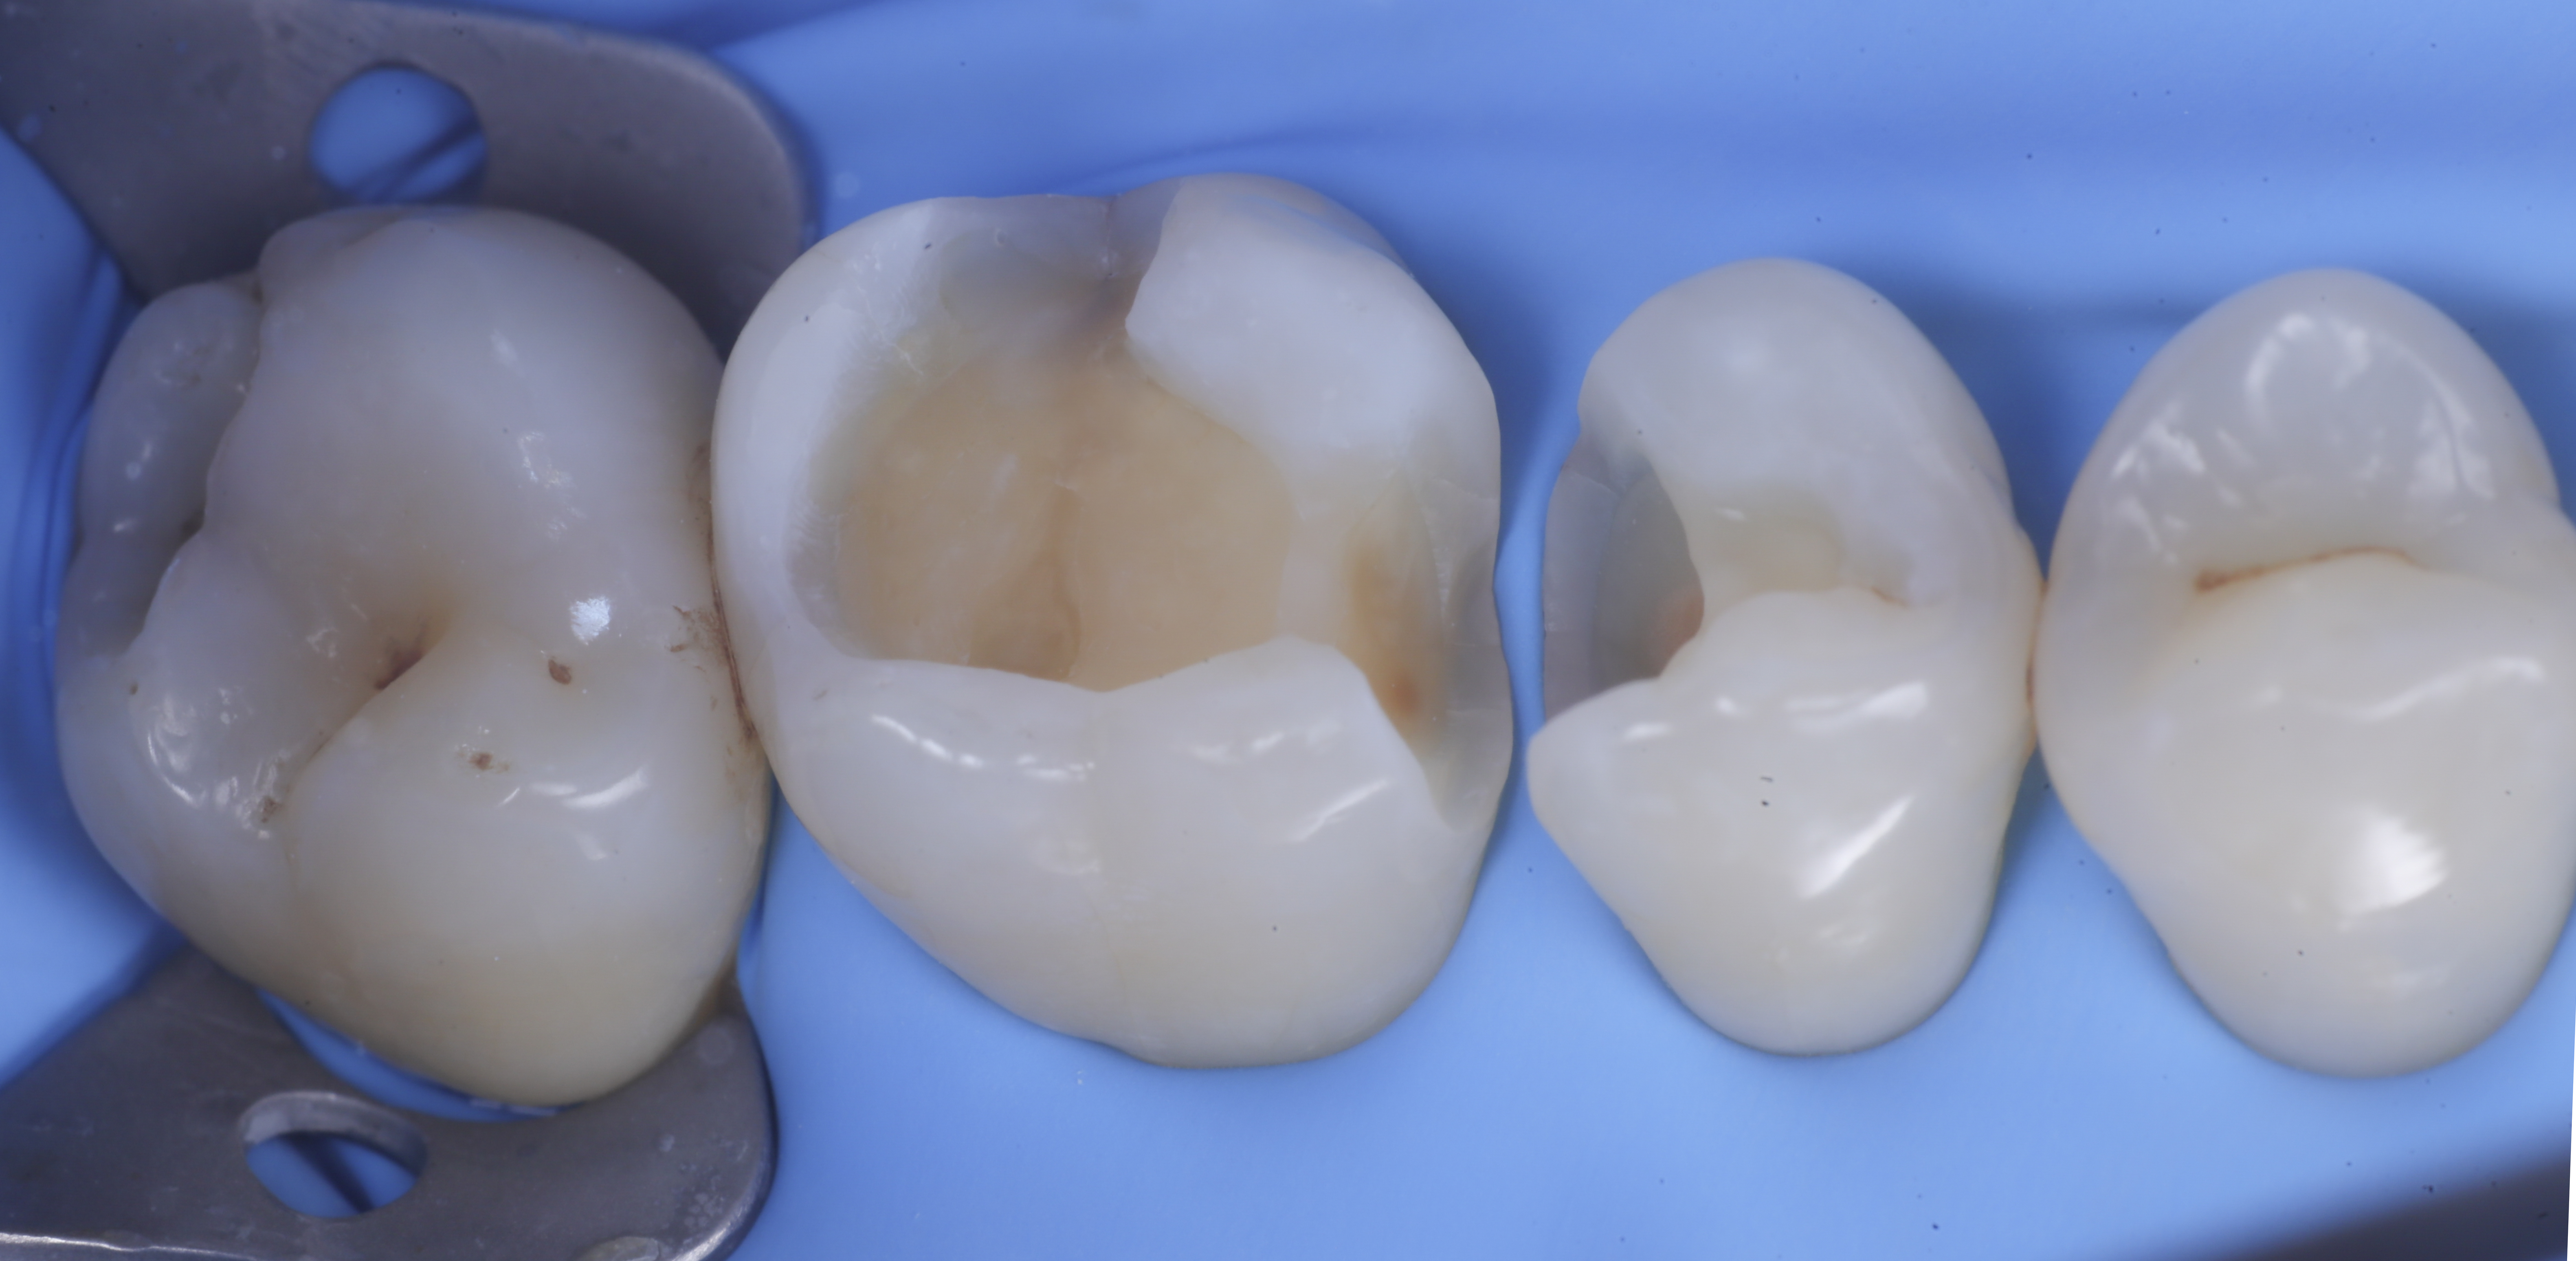

foto 2 Isolamento e aspetto delle cavità ultimate

foto 3 Aspetto vestibolare della cavità ultimate

foto 4 Aspetto della chiusura cervicale e sulle pareti assiali dato dalla prima matrice